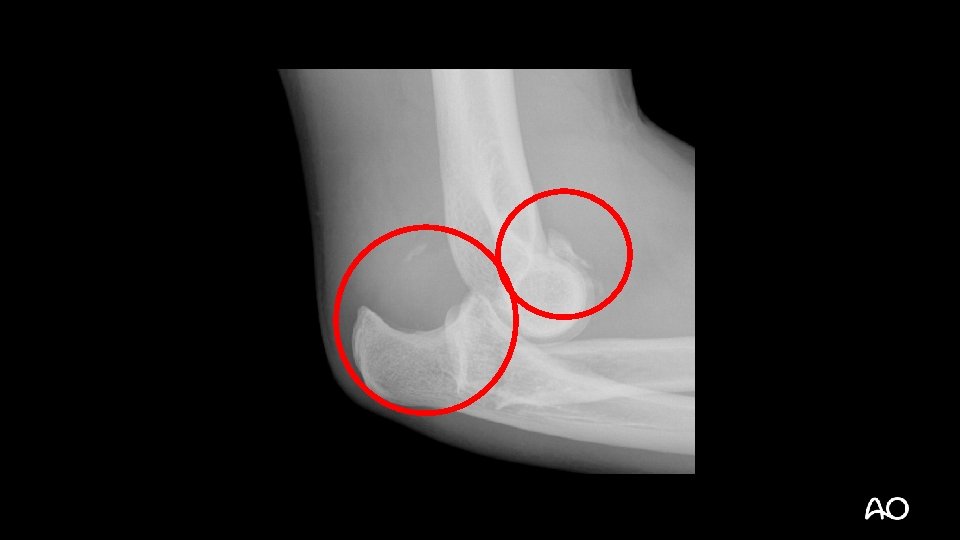

Varus posteromedial fracture dislocation • Recently described injury pattern • Failure to recognize can result in poor outcomes (arthrosis) • Easy to overlook (occasionally small coronoid fractures)

Varus posteromedial fracture dislocation Courtesy of David Ring • Stress views demonstrate that the LCL is ruptured and the elbow is unstable • Results can be poor without operative treatment